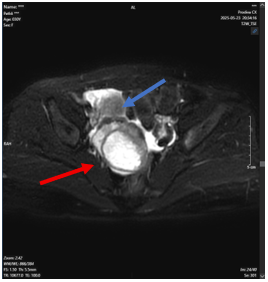

Ca lâm sàng: Điều trị thành công bệnh nhân ung thư tuyến giáp đã di căn xương cột sống sau 16 năm tại Trung tâm Y học hạt nhân và Ung bướu

GS.TS. Mai Trọng Khoa, PGS.TS. Phạm Cẩm Phương, Ths Lê Quang Hiển, BS. Vũ Thị Huyền Trung tâm Y học hạt...